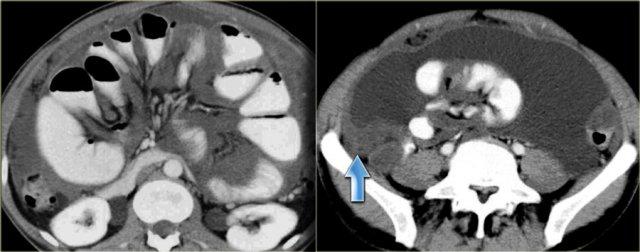

Bên trái là một trường hợp giả u nhầy phúc mạc khác.

Có hiện tượng chèn ép mạc treo dẫn đến mạc treo dày lên dạng bánh, tăng tỷ trọng (mũi tên).

Ngoài ra còn có một số vôi hóa.

Giả u nhầy phúc mạc thường bị nhầm lẫn với ung thư biểu mô nhầy phúc mạc.

Khác với ung thư biểu mô phúc mạc, giả u nhầy phúc mạc không có các ổ di căn mạc nối thực sự biểu hiện dạng bánh mạc nối hoặc các ổ di căn phúc mạc.